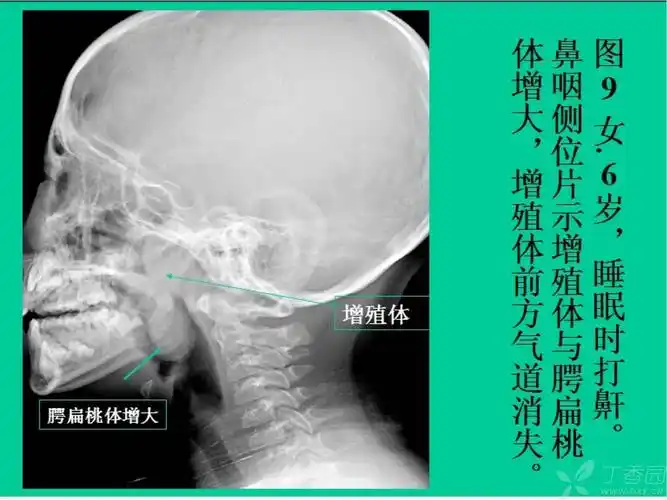

请大家帮忙分析一下腺样体肥大的影像表现,有没有正常的图片 [病例帖]